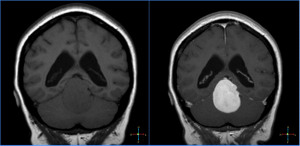

Image IQ Quiz: Patient Presents with Dizziness

Can you diagnose this patient with dizziness?